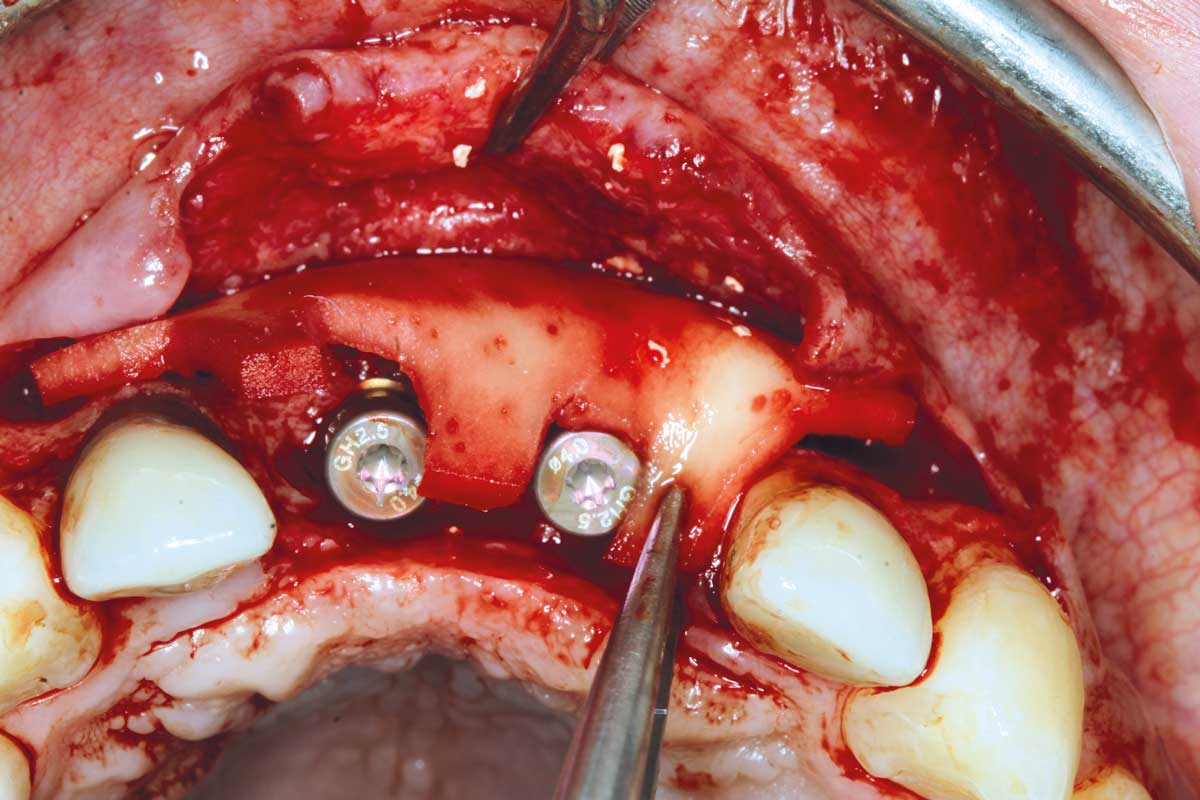

17/26 - Insertion of two Straumann BLX implants 3.75 x 14 mm / 3.75 x 12 mm

Ridge augmentation in the maxilla with maxgraft® bonebuilder in the aesthetic zone - Dr. M. Kristensen